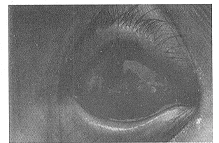

体检:体形稍胖,面色白。胸部X线片心肺未见异常,心电图正常。实验室检查:血白细胞4.4×109/L,中性0.67,单核0.1,淋巴0.11,嗜碱细胞0.04,嗜酸细胞0.08。空腹血糖8.6mmol/L,餐后21mmol/L。尿糖(+)。在溃疡面上刮取坏死组织作涂片检查,见真菌菌丝。真菌培养属酵母菌属中隐球菌感染。治疗:给予二性霉素B每天0.2mg/Kg,静脉滴注6d。胰岛素早餐前8u、中餐前6u、晚餐前6u分别皮下注射治疗。3%硼酸水清洗双眼后,再用细棉签蘸2.5%碘酒涂溃疡面,每日2次,注意不能误及正常角膜。3d后病状明显好转。7d出院时,患者右眼视力0.2,左眼0.08。双结膜充血基本消失。右眼角膜溃疡面变平,浸润消失,恢复透明(图2)。左眼溃疡面缩小,色变淡,浸润消失。空腹血糖6.8mmol/L,餐后12.3mmol/L。尿糖(-)。溃疡面刮取组织涂片检查未见真菌菌丝。出院后每半月随访1次。血糖、尿糖均正常,双角膜溃疡愈合,左眼遗留斑翳。随访3月时,右眼视力0.2,左眼0.1。双眼角膜炎未见复发。

图2 治疗后